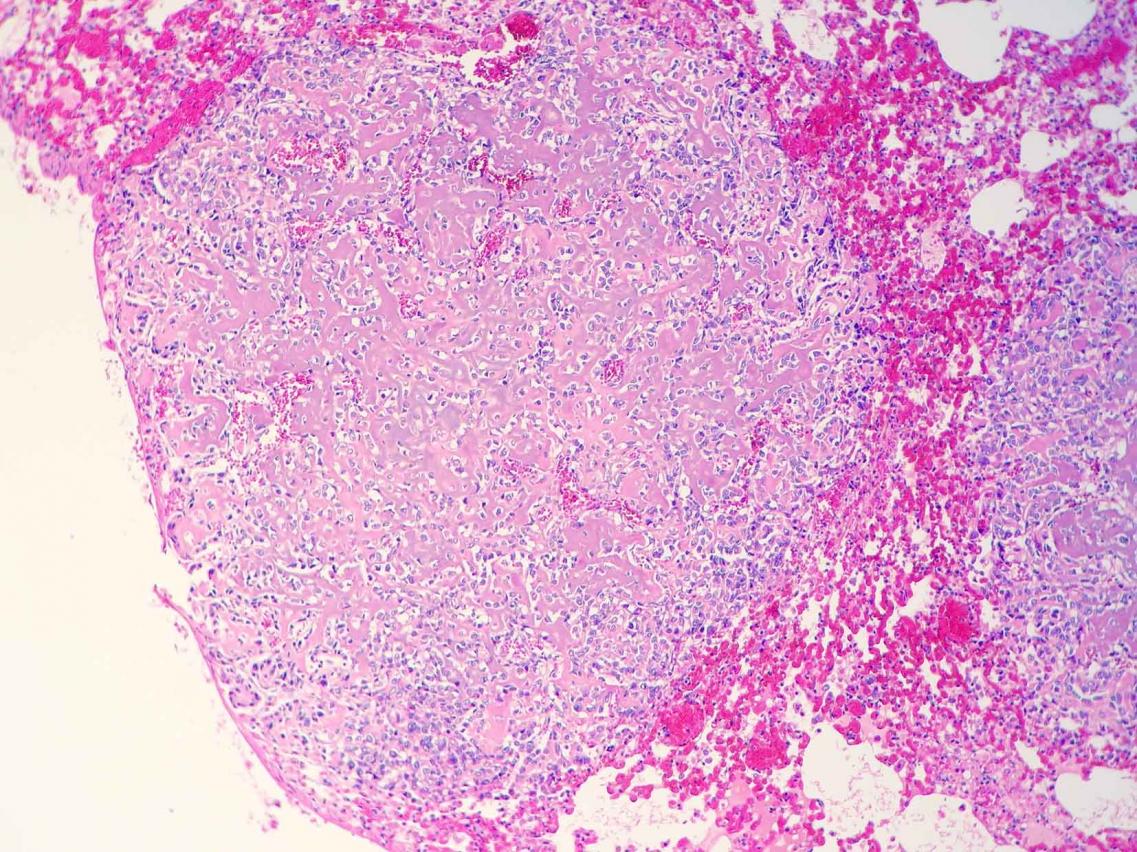

Este estudio retrospectivo fue encaminado por Celic Berenice Montoya, estudiante de especialidad del Departamento de Patología de la Facultad de Veterinaria de la prestigiosa UNAM de México, durante su rotación en Noah's Path en 2017. En el mismo, publicado recientemente en la Revista de Clínica Veterinaria de Pequeños Animales de AVEPA, se describen 6 casos de condrosarcoma en cobayas con predilección por huesos planos y, en 3 de los pacientes, metástasis. Los condrosarcomas se observan en cobayas con mayor frecuencia que en el resto de mamíferos exóticos, en los que son muy raros.